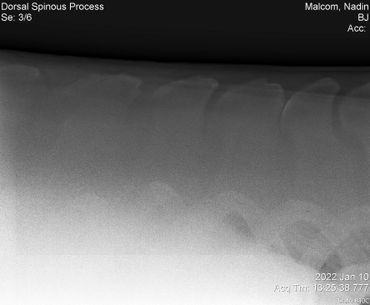

Update 03/04/2022 Billie Jean kept showing some severe sensitivity every time we touched her on her withers and along her spine so back in January we had x-rays taken to check for kissing spine. Everything looked great so we treated her for ulcers with Gastrogard paste and Sucralfate for 7 days.

Her vet bill from January 10 was $445